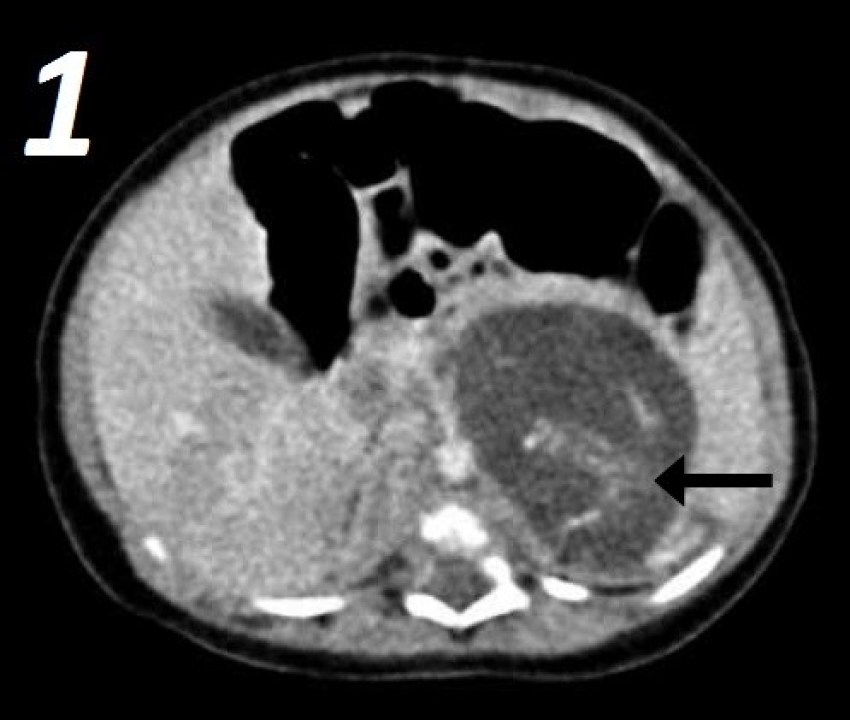

According to the researchers, a baby girl who was born in 2010 was thought to have had two tumors in her abdomen. However, after extensive research is has been found that she actually had twin fetuses.

The fetuses are believed to have ranged from 8 to 10 weeks old in side of her, according to the researchers, and weighed approximately half an ounce and a third of an ounce.

The report confirms that all organs were connected through an umbilical cord to a single placenta-like mass.